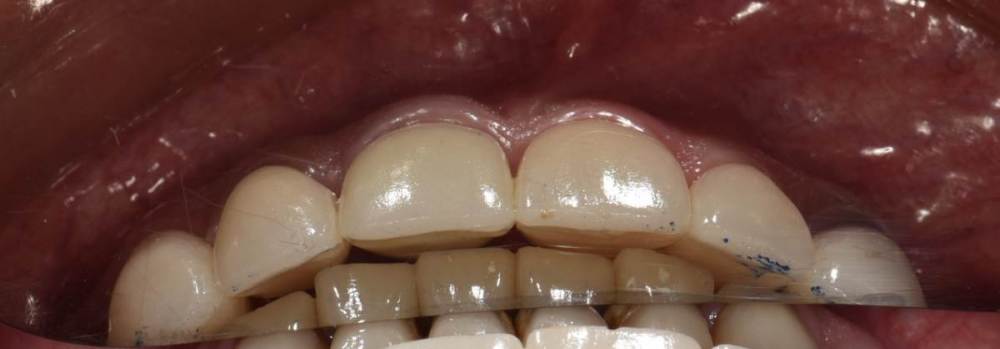

Пару дней назад сделали перенос воскового моделирования в полость рта с помощью силиконовый ключей.

Улыбка до:

IMG_0634.thumb.jpg.5ffaa548d0888778b0f37eea7c1e219e.jpg

Улыбка после(стоит анестезия, на губу не обращаем внимания):

464983353_IMG_0833(2).thumb.JPG.6fc1756f43caeb2ff7b9787b9c74bee1.JPG

Перенос был без препарирования передних зубов, поэтому пациент оценивает только форму и функцию. На цвет не обращаем внимания.